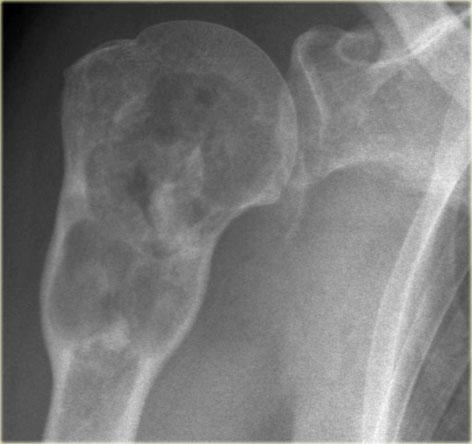

Ở bên trái là tổn thương tiêu xương thùy múi, một phần không rõ ranh giới ở đầu trên xương cánh tay.

Sự hiện diện của các vôi hóa gợi ý đây là một khối u sụn.

Các phần tiêu xương có xâm lấn và phá hủy vỏ xương nên làm tăng nghi ngờ về sarcoma sụn độ cao.